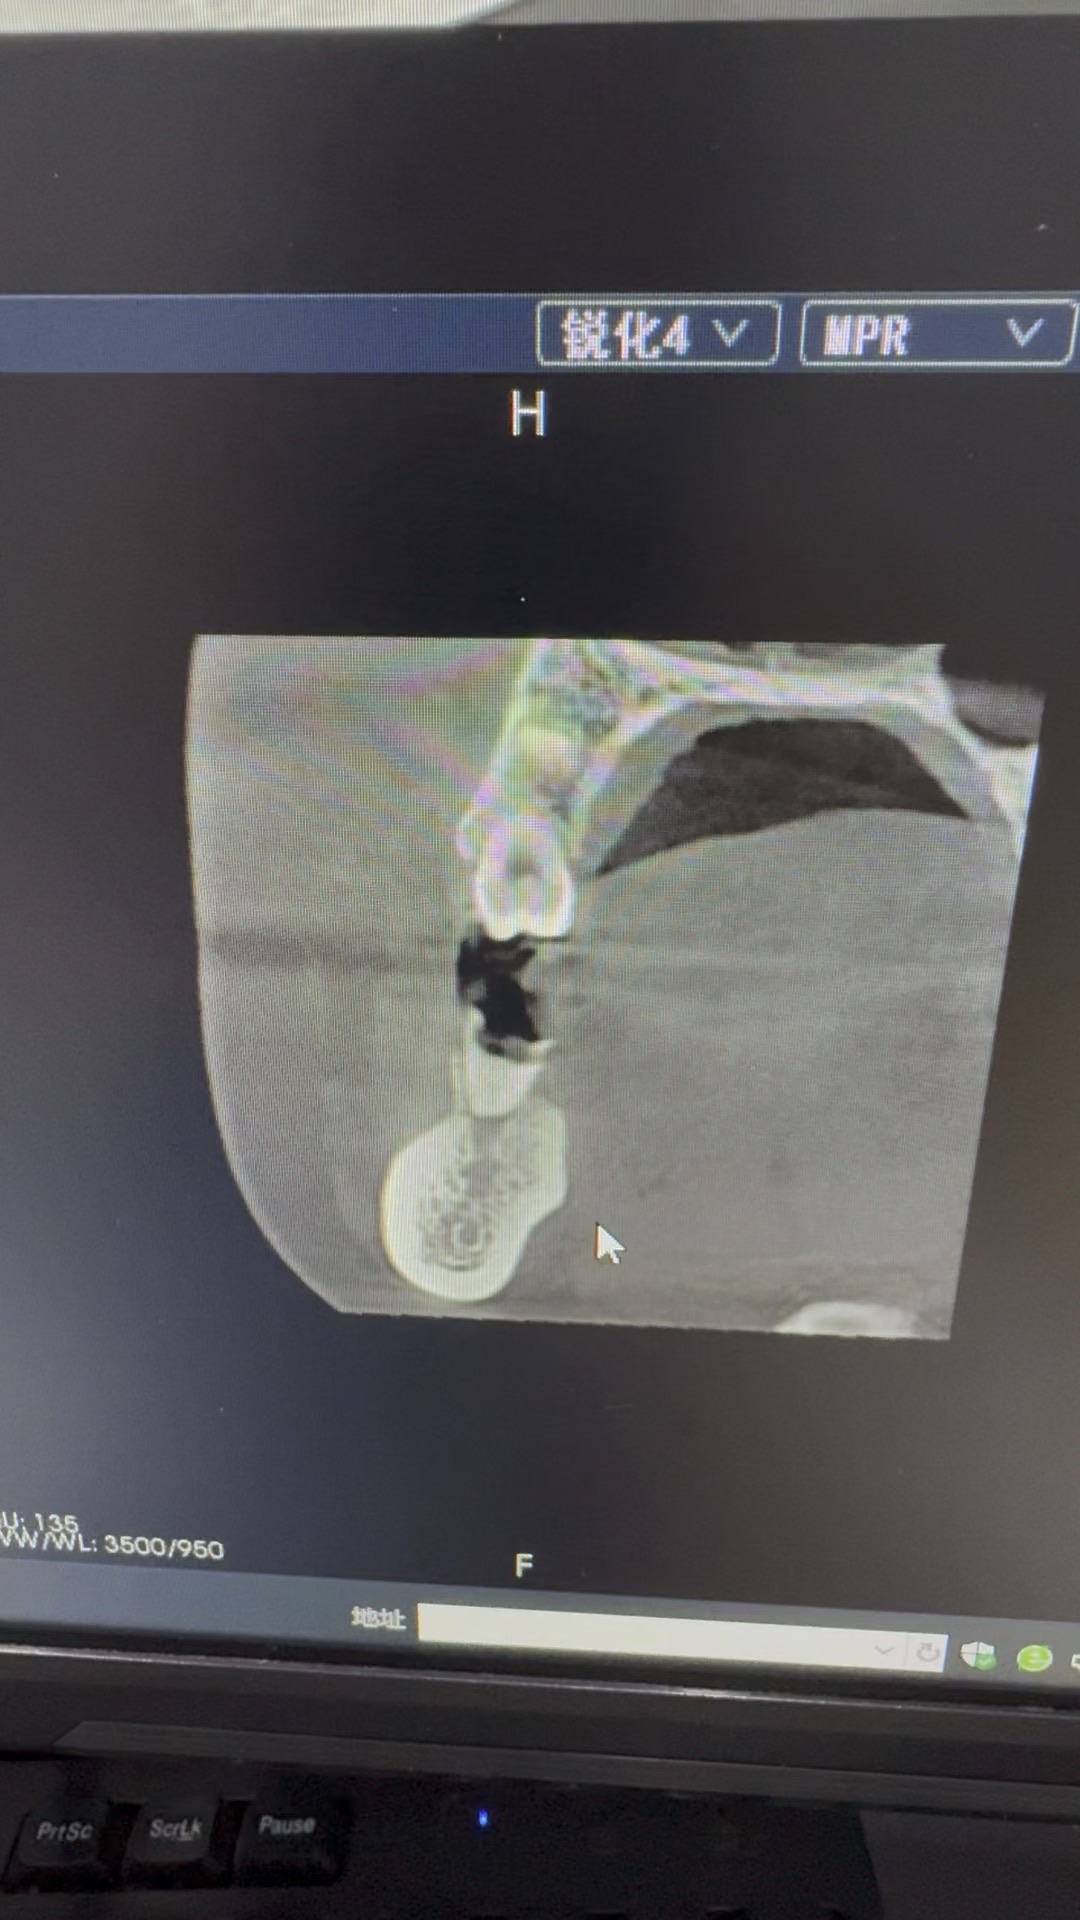

口腔2 条热帖已更新